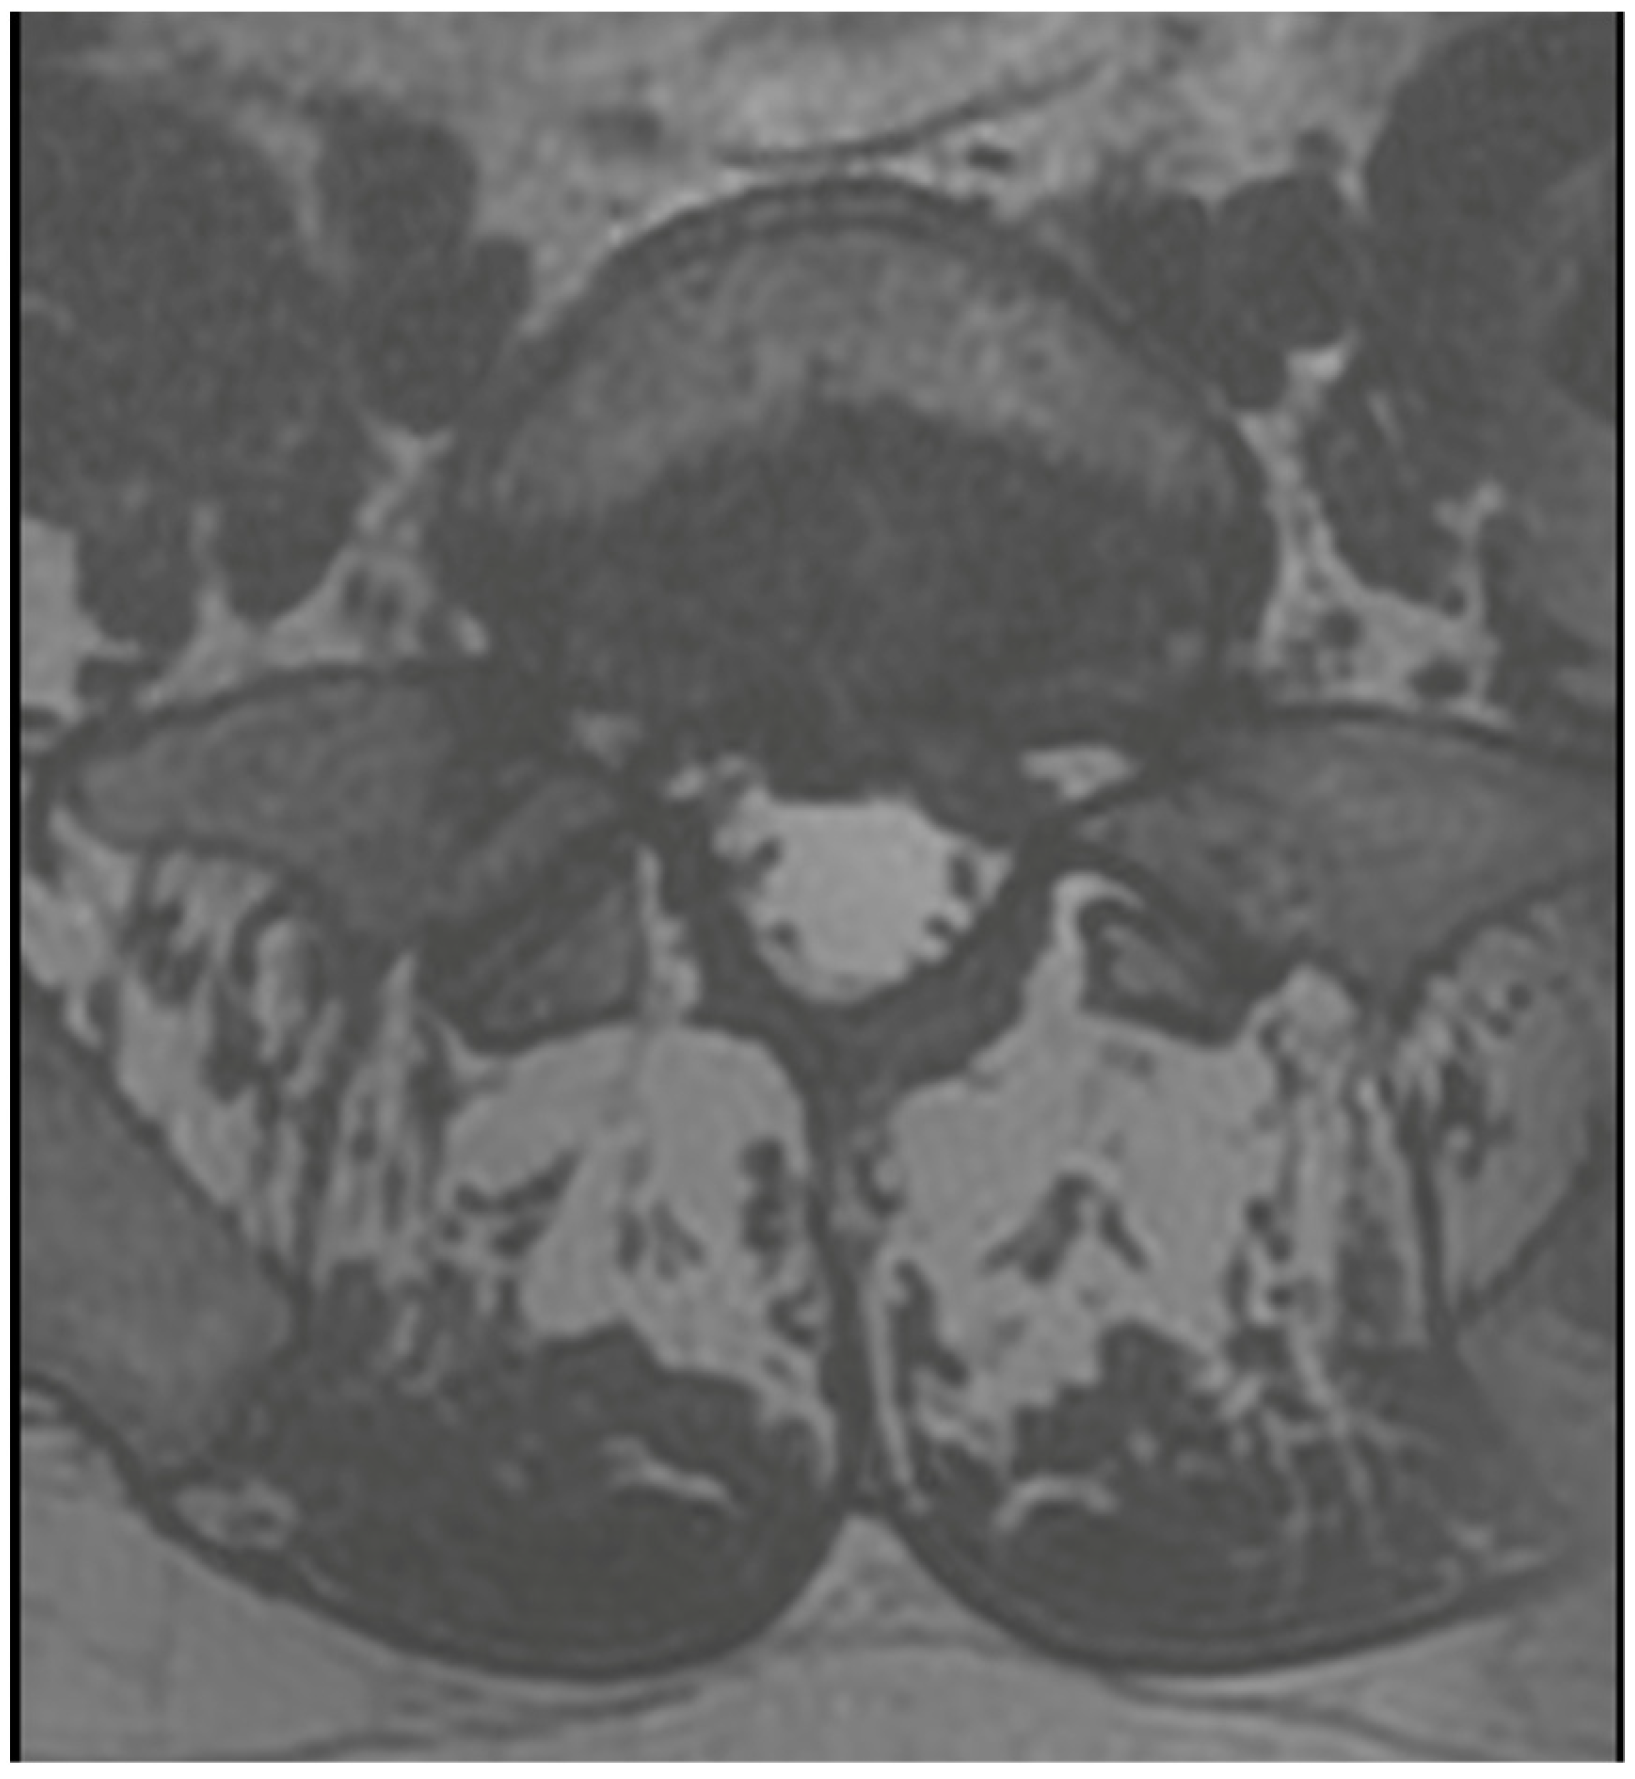

3.4. Case 1: Transient Cauda Equina Syndrome Due to Subdural Hematoma

- Case 1: Incidents of postoperative cauda equina syndrome are documented in the context of traditional surgical approaches. In our literature review, we identified a singular case of postoperative cauda equina syndrome, which, however, pertained to a patient following endoscopic intervertebral stabilization. This incident was associated with the migration of bone material into the dural sac [43]. Our case suggests that previous surgery, leading to scarring and adhesions, and anatomical challenges such as steep and large facet joints, might have contributed to the complication by complicating root mobilization and endoscope trajectory.